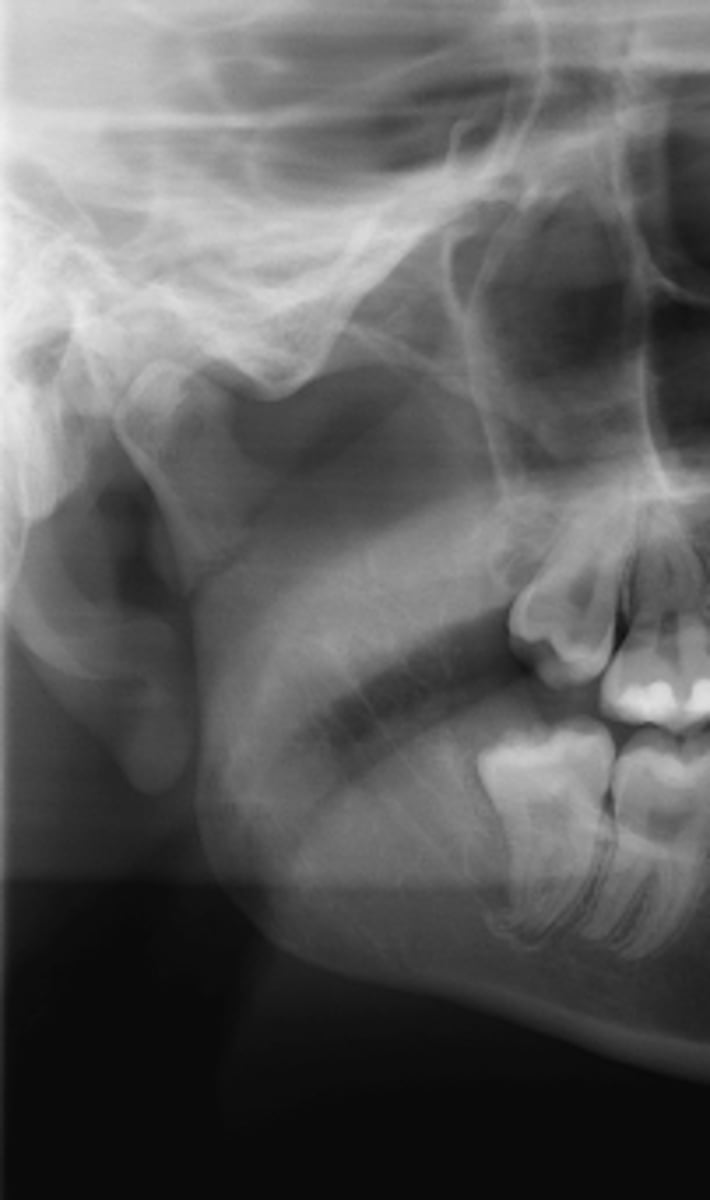

Subcondylar

PANOREX showing this fracture pattern. Where is this fracture located?

- Angle

- Subcondylar

- Body

- Coronoid

- Ramus